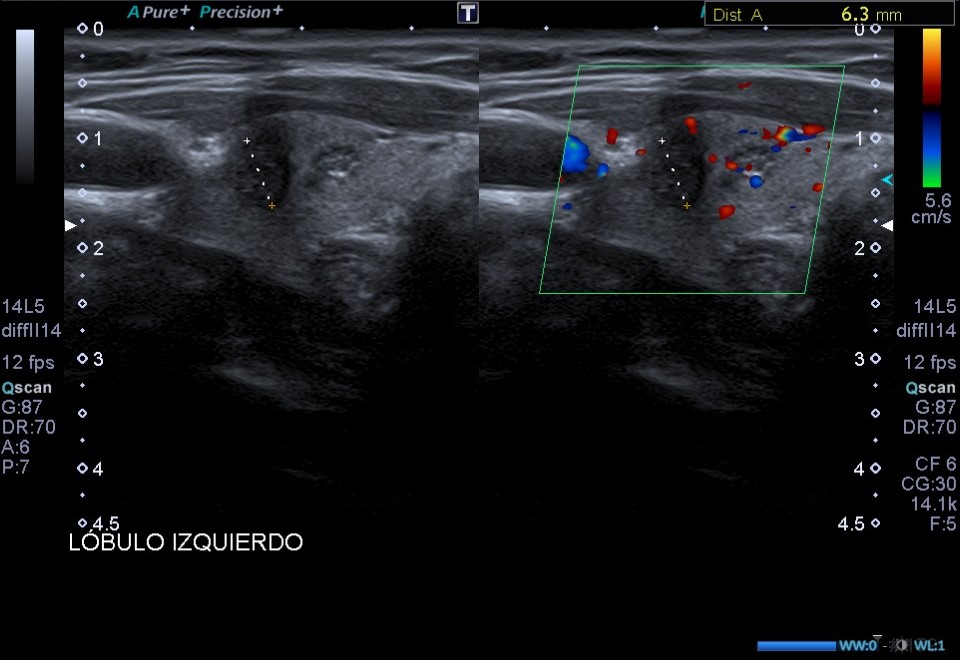

Ecografía de tiroides en consulta: En el LTI presenta dos lesiones nodulares en el área central del lóbulo tiroideo, presentando ambas un aspecto heterogéneo, bordes y márgenes mal definidos y microcalcificaciones.

Dada la presencia de nódulos tiroides con patrones ecográficos de alta sospecha de malignidad (bordes y márgenes mal definidos y presencia de microcalcificaciones), se solicita ecografía tiroidea reglada, y derivar a especialista en función de resultados.